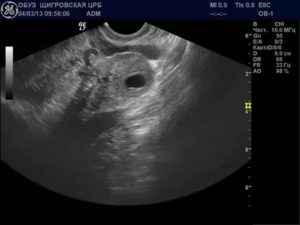

На УЗИ желтое тело определяется как округлое неоднородное образование.

Его видно и при методике исследования через брюшную стенку (трансабдоминальная методика УЗИ), но более достоверные результаты диагностики получают при трансвагинальном методе с использованием внутривагинального датчика.

Становится видно желтое тело в яичнике после завершения овуляции. После выхода яйцеклетки фолликулярная жидкость выливается, полость фолликула смыкается. В ней сразу формируется железистая эндокринная структура, в первые дни она небольшого размера.

Желтое тело в яичнике и задержка

При появлении задержки менструации при проведении УЗИ врач должен оценить размеры и структуру образования, которое появляется во 2 фазе. Отсутствие месячных в срок при наличии лютеиновой железы может быть обусловлено беременностью. В норме размер ее должен быть 20-30 мм. На УЗИ она выглядит как гиперэхогенное образование с неоднородным содержимым.